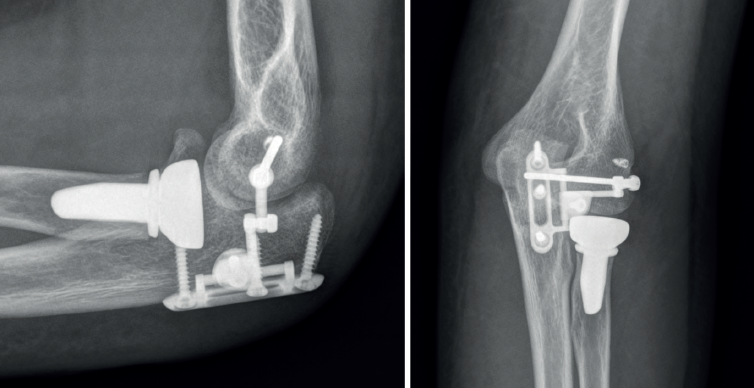

Tras realizar este paso, se realiza la reparación del resto de las estructuras. Al concluirla, se verifica la estabilidad y la congruencia articular a lo largo de todo el arco de movilidad en flexoextensión y, si se evidencia inestabilidad franca, se procede a la colocación del dispositivo según está descrita la técnica por el fabricante (Figura 7).